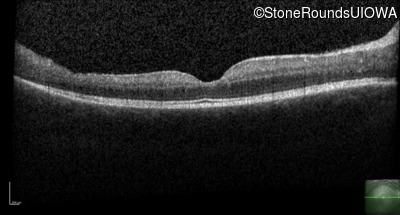

Optical Coherence Tomography - Right - 20/50

Exemplar / OCT Stack